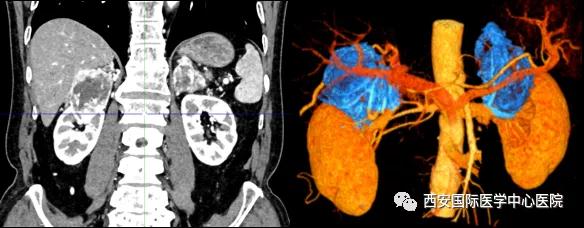

7月15日,西安國(guó)際醫(yī)學(xué)中心醫(yī)院泌尿外科楊增悅教授團(tuán)隊(duì)成功完成“機(jī)器人輔助根治性右腎、右腎上腺部分切除 左腎上腺切除 腎門(mén)淋巴結(jié)清掃術(shù)”。此臺(tái)手術(shù)涉及三個(gè)器官:右腎切除、右側(cè)腎上腺轉(zhuǎn)移瘤切除(保留部分正常腎上腺組織)、左腎上腺切除,并且清掃了腎門(mén)淋巴結(jié)。

今年七十五歲的患者,來(lái)自陜西省商洛市,四月前因腰背部疼痛就診于當(dāng)?shù)蒯t(yī)院,行CT檢查發(fā)現(xiàn)“右腎、雙側(cè)腎上腺占位,前縱膈淋巴結(jié)腫大,雙肺多發(fā)結(jié)節(jié)、胸椎骨質(zhì)破壞,考慮轉(zhuǎn)移瘤”。為進(jìn)一步診斷治療,患者的兒子帶他來(lái)到西安某三甲醫(yī)院,查泌尿系CT提示“右腎占位性病變,多考慮腎癌,雙側(cè)腎上腺多發(fā)轉(zhuǎn)移灶,腹膜后多發(fā)腫大淋巴結(jié)”;行穿刺活檢提示“腎透明細(xì)胞癌”;并給予患者口服靶向藥物的治療方案。

自四月份至今,患者一直口服靶向藥物治療(阿昔替尼5mg 2次/日),期間無(wú)不良反應(yīng),目前腰背部疼痛癥狀也有所緩解,復(fù)查影像學(xué)資料提示瘤體較前縮小,腫瘤完整切除的可能性明顯提高;而且患者的兒子也是一名外科醫(yī)生,所以他更想為父親完成后續(xù)的手術(shù)治療。

患者一家慕名前來(lái)到西安國(guó)際醫(yī)學(xué)中心醫(yī)院找到楊增悅教授。楊增悅教授仔細(xì)看完患者的之前的影像學(xué)及病理資料后,診斷為:右腎透明細(xì)胞癌(T4N1M1);并安排他住院。而后,主管醫(yī)生及時(shí)為他完善了術(shù)前檢查及評(píng)估。7月15日,在麻醉手術(shù)中心柴偉主任、王彬榮副主任、李娟護(hù)士長(zhǎng)、李瑞剛護(hù)士長(zhǎng)及全體麻醉手術(shù)中心團(tuán)隊(duì)的有力保障下,成功完成了這臺(tái)“大”手術(shù)。

手術(shù)由楊增悅教授主持,舒濤主治醫(yī)師、王東主治醫(yī)師主刀,黃怡醫(yī)師、王平醫(yī)師協(xié)助完成。由于第四代達(dá)芬奇機(jī)器人更加靈活和精準(zhǔn)的特性,手術(shù)全程順利,尤其是完全精準(zhǔn)的“解鎖”了右腎動(dòng)脈和右腎靜脈的數(shù)十根交互纏繞的分支血管。術(shù)后患者麻醉恢復(fù)后生命體征平穩(wěn),順利返回泌尿外科普通病區(qū)進(jìn)一步康復(fù)。